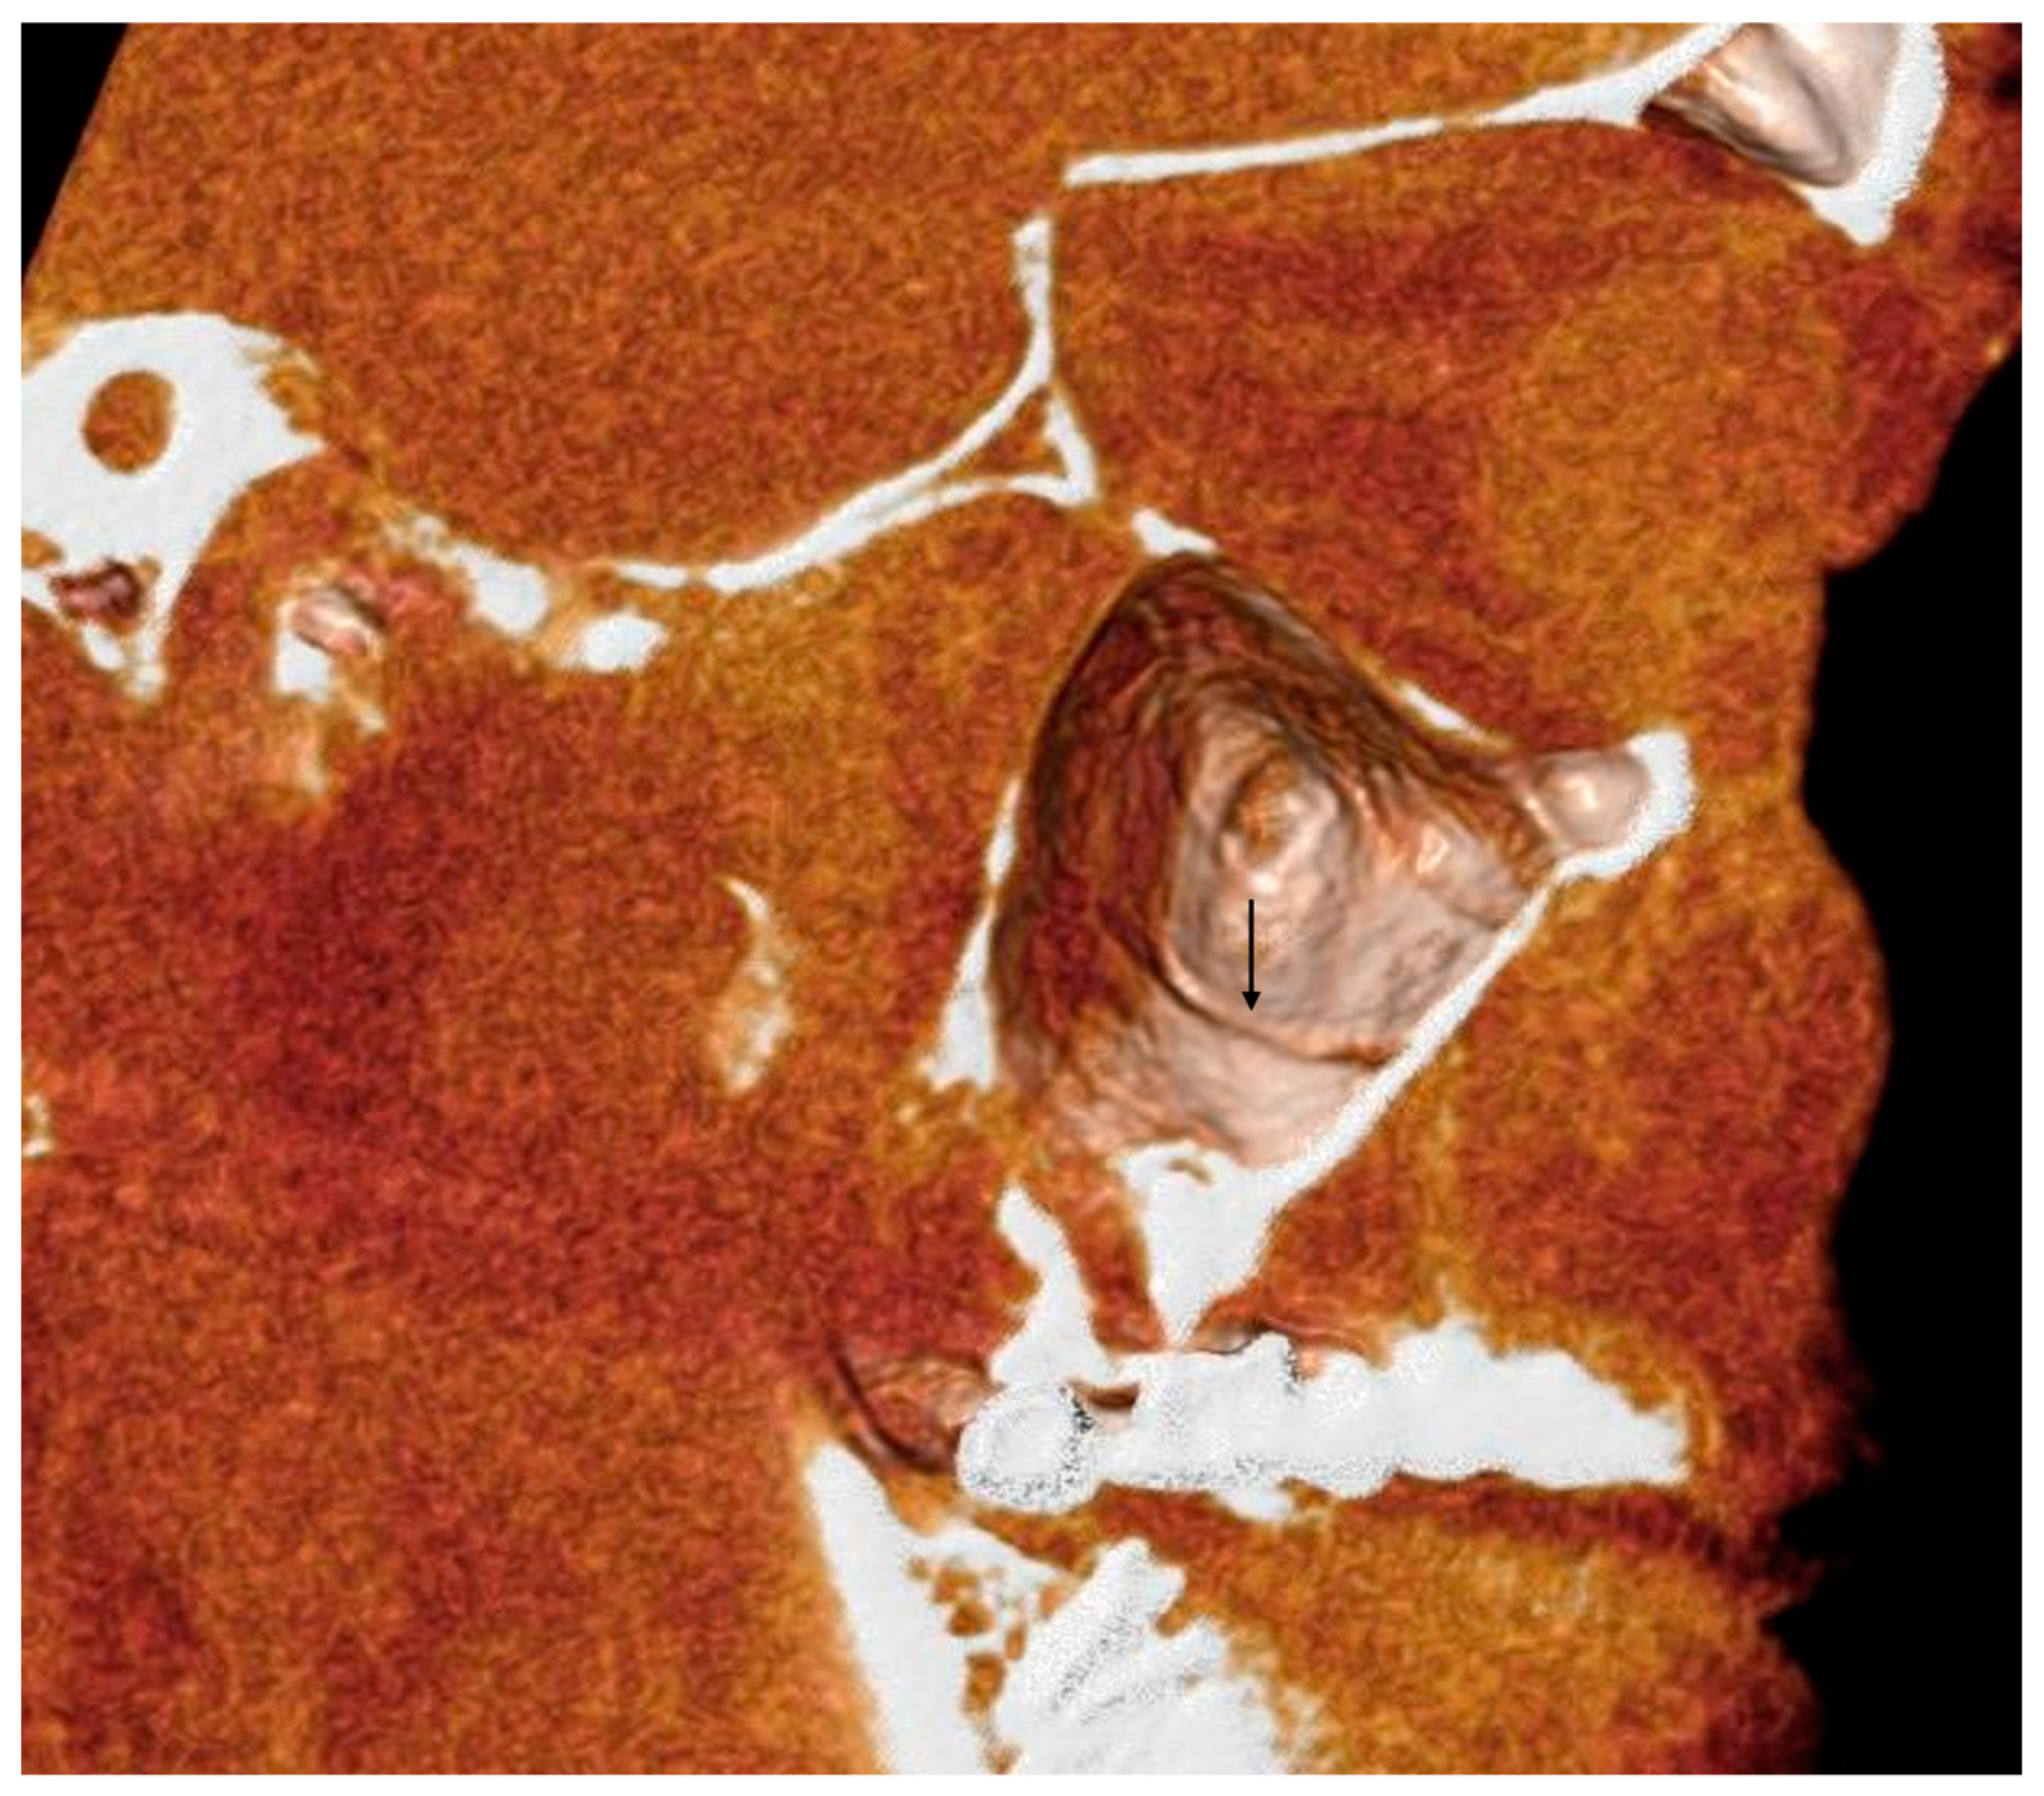

- The length of the arterial pathway in the mesiodistal dimension, on cross-section setting at 1 mm (Figure 2);

- The height of the maxillary bone crest in the cranio-caudal direction, on cross-section at the level of the first superior molar (Figure 3);

- The sized branches of the alveolar antral artery at the level of the first superior molar.